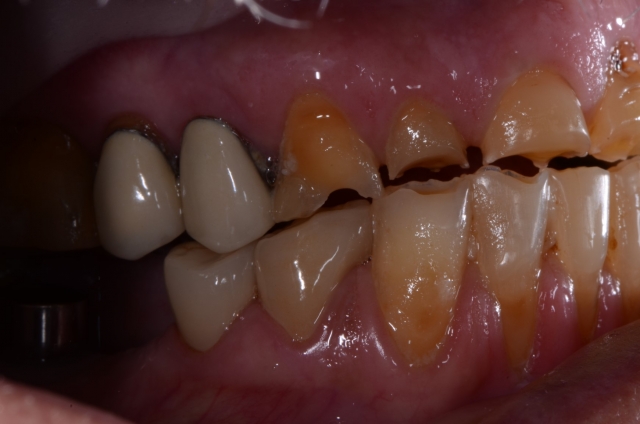

During the oral examination, I recognized that Roger had three of the syndromes we discussed above: extreme worn dentition, xerostomia, and GERD. The damage was extensive and left his dentition in an extremely catastrophic state.

At this point, my job was to educate him as to the true state of his dentition. A patient doesn’t always recognize the gravity of the situation until it’s too late; it becomes our responsibility to inform them and educate them as to the consequences of these conditions.

This is a great time to enlist the skills taught at Spear. The Treatment Planning With Confidence course specifically equips dentists to address these challenges. For example, knowing how to illustrate the patient’s true condition with 35 mm photography is a powerful teaching tool that not only identifies the disease processes but also effectively educates the patient as to their best restorative option.

Worn dentition is rarely the sole contributor of terminal dentition; it’s usually a co-morbid factor with xerostomia and GERD. Worn dentition is one of those subtle disease processes that can sneak up on you and your patient. Many times, you may wonder, “When do I say something about a patient’s excessive wear?” I try to relate the consequences to worn dentition as soon as I see signs of wear.